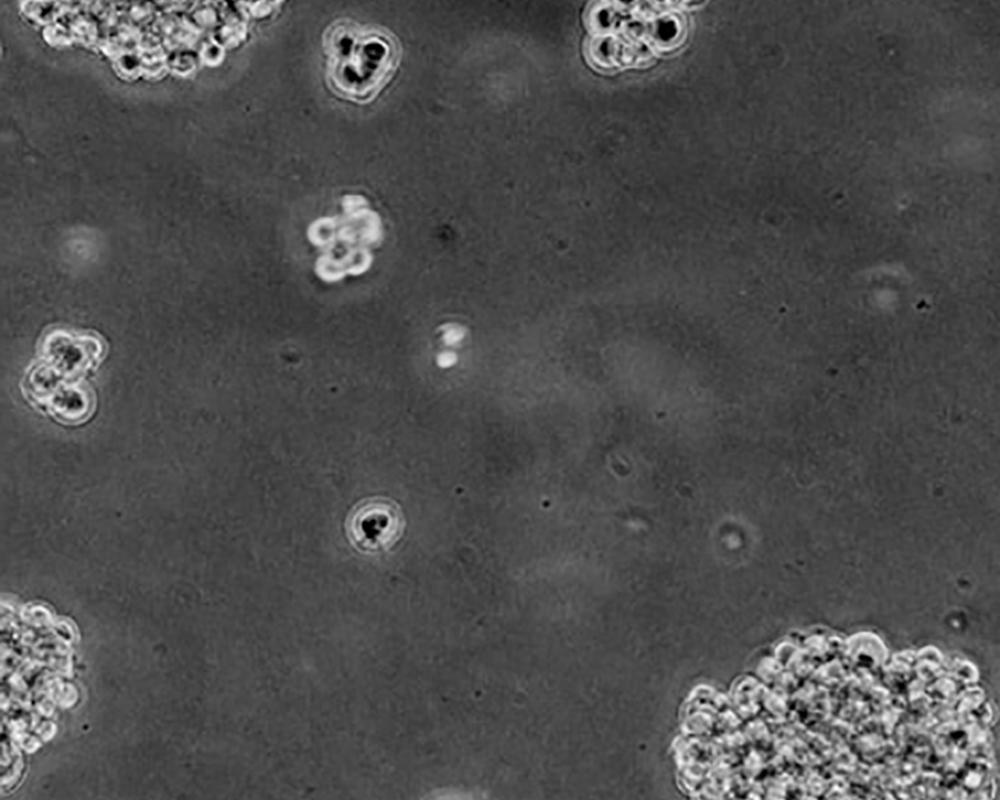

生長(zhǎng)特性 clusters in suspension

形態(tài)特征 spherical

細(xì)胞描述 該細(xì)胞由Oettgen F及其同事從一名29歲的患有廣泛、快速進(jìn)展性惡性黑色素瘤的白人男性患者的胸導(dǎo)管中分離建立的。該細(xì)胞可產(chǎn)生黑色素,電鏡檢測(cè)發(fā)現(xiàn)細(xì)胞中色素顆粒與自身合成和吞噬作用相關(guān)。在63%的惡性黑色素瘤患者和10%其他疾病患者體內(nèi)發(fā)現(xiàn)了針對(duì)該細(xì)胞系的抗體。